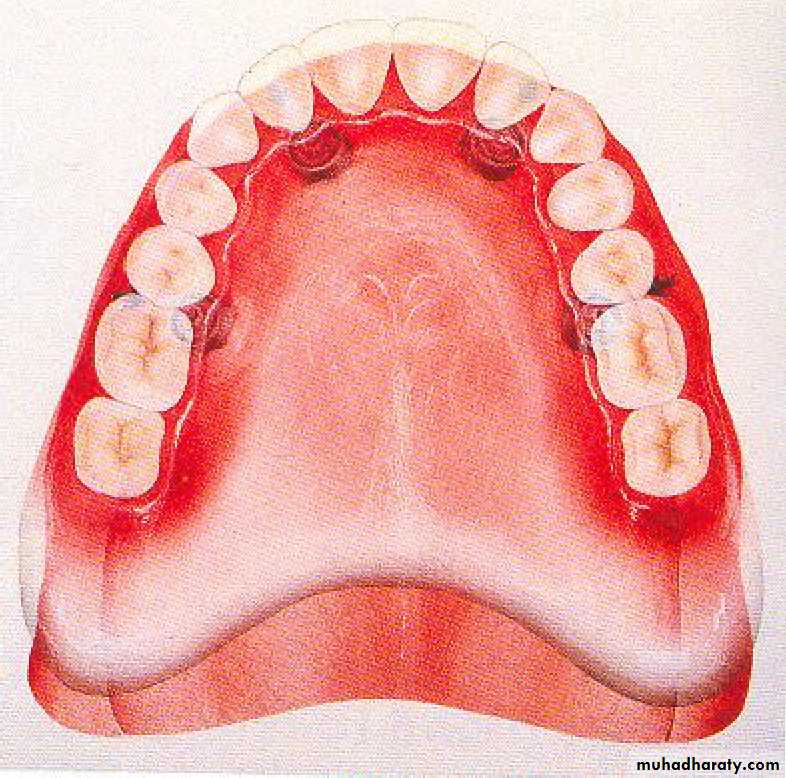

• Tooth supported

• Implant supported• 1) Tooth supported overdentures.

• 1- Simple tooth modification of vital abutment.

• A- Thimble-shaped

• coping• 2- Tooth reduction and cast coping of vital abutment

• B- Tooth reduction• and cast coping

• 2- Tooth reduction and cast coping of vital abutment